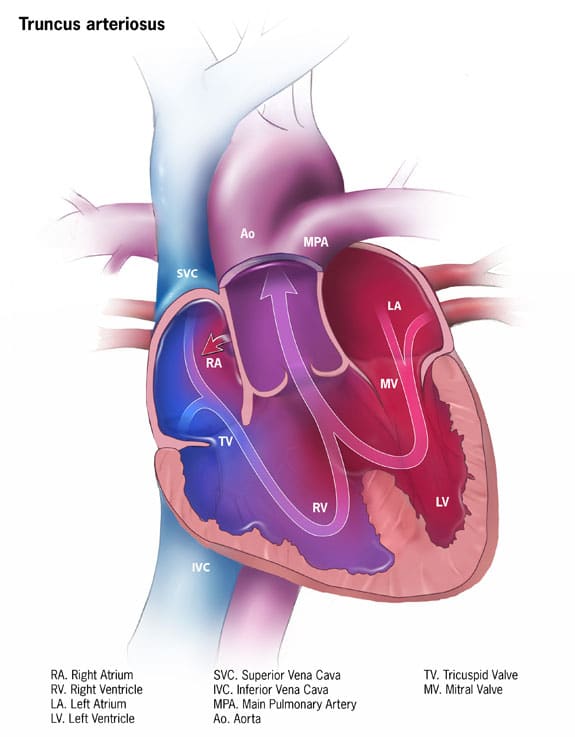

Patent Truncus Arteriosus

Mixed (Cardiac) Heart Defects